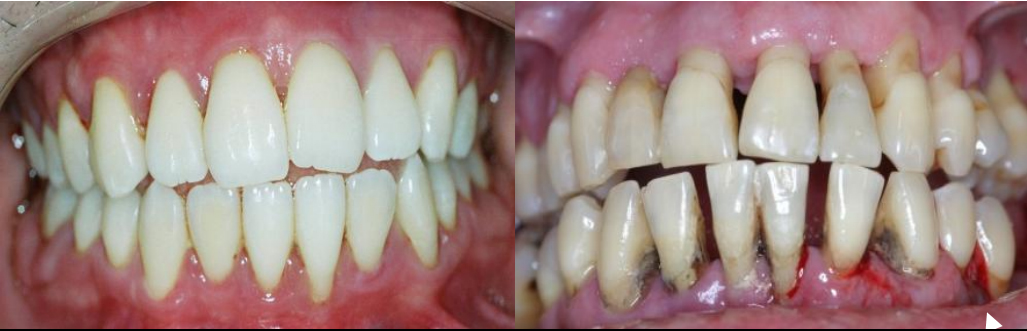

O que acontece se a periodontite agressiva não for tratada adequadamente?

A falta de tratamento adequado pode levar à perda óssea severa, mobilidade dentária e, eventualmente, à perda dos dentes. Além disso, a infecção pode se espalhar e afetar a saúde geral do corpo, sendo fundamental buscar o tratamento para a interrupção da destruição dos tecidos periodontais.

Quando a doença periodontal é muito avançada ou não responde completamente às terapias não cirúrgicas, procedimentos cirúrgicos podem ser indicados. Cirurgias de retalho permitem ao dentista acessar áreas mais profundas para remover tártaro e inflamação. Em casos de perda óssea significativa, enxertos ósseos ou o uso de materiais regenerativos podem ser tentados para tentar recuperar parte do suporte perdido.